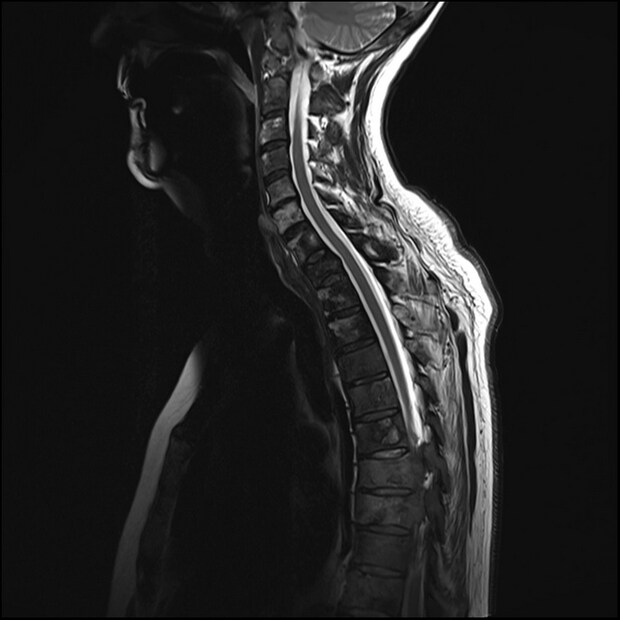

মেরুদণ্ডের ক্ষতি করতে পারে ক্যান্সার স্পাইনাল কর্ড আক্রান্ত হলে পেশীতে সমস্যা দেখা দিতে পারে, যেমন পা, গোড়ালি এবং পায়ের পেশীর টিস্যু শক্ত হয়ে যাওয়া। মেরুদণ্ডে যে কোনও ধরনের টিউমার হতে পারে। বেশিরভাগই প্রাথমিক টিউমারই দেখা দেয় এবং তা ধীরে ধীরে বৃদ্ধি পায়। সেকেন্ডারি টিউমার হল ক্যান্সার কোষ যা শরীরের অন্যান্য অংশ থেকে আসে। কিছু মূল ক্যান্সার যা মেরুদণ্ডে ছড়িয়ে পড়ে তার মধ্যে রয়েছে প্রোস্টেট, ফুসফুস এবং স্তন ক্যান্সার। দুই ধরনের ব্লাড ক্যান্সার, যেমন মায়লোমা এবং লিউকেমিয়াও মেরুদণ্ডে ছড়িয়ে পড়ে বলে জানা গেছে। এটি সাধারণত অস্থি মজ্জার ভিতরের শ্বেত কোষ বা রক্তরস কোষে ম্যালিগন্যান্সির উৎপত্তির কারণে হয়।

এর ফলে কী হতে পারে? ক্যান্সার মেরুদণ্ডে ছড়িয়ে পড়লে রোগীরা চেতনা হারাতে পারে। এর সঙ্গে পেশীর মোচড় বা শিথিল হওয়া, শরীরের কার্যকারিতা নিয়ন্ত্রণের সম্পূর্ণ ক্ষতি, মূত্রাশয়ের নিয়ন্ত্রণ হারানো নানা সমস্যা দেখা দিতে পারে। রোগীরা পিঠে ব্যথা অনুভব করতে পারেন যা সময়ের সঙ্গে সঙ্গে ভয়াবহ দিকে যেতে পারে। প্রায়শই মাঝখানে বা নীচের পিঠে ব্যথা হয় এবং ব্যথার ওষুধে কোনও কাজ হয় না। শুয়ে থাকার সময় এই ব্যথা আরও বাড়ে এবং নিতম্ব বা পায়ের দিকে প্রসারিত হতে পারে। আক্রান্ত ব্যক্তিরা পায়ের পেশীর দুর্বলতাও অনুভব করতে পারেন। যার ফলে হাঁটতে গিয়ে পড়ে যাওয়া, হাঁটার সমস্যা এবং পক্ষাঘাত হতে পারে।